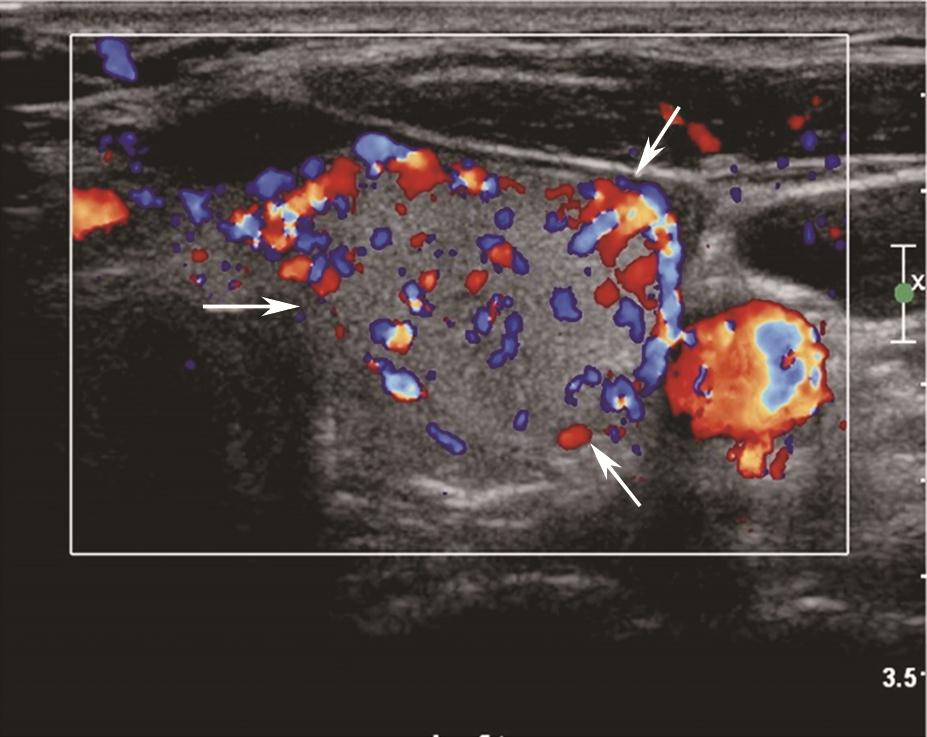

(五)Graves病

甲状腺呈弥漫性、对称性增大,包膜规则。腺体回声因病程和治疗情况而有所不同。未经治疗者,腺体回声均匀减低,少数呈散在、局灶性减低;病程长及反复发作者,腺体回声正常或稍强。腺体内可见多个管状无回声区(血管扩张)。彩色多普勒显示甲状腺内血流信号极为丰富,呈“火海征”(图3)。频谱多普勒可见甲状腺上、下动脉血流速加快,收缩期峰值流速多超过70cm/s(正常为30cm/s)(图4)。

图3右侧颈部纵切面:甲状腺右叶腺体血流信号丰富,呈“火海征”